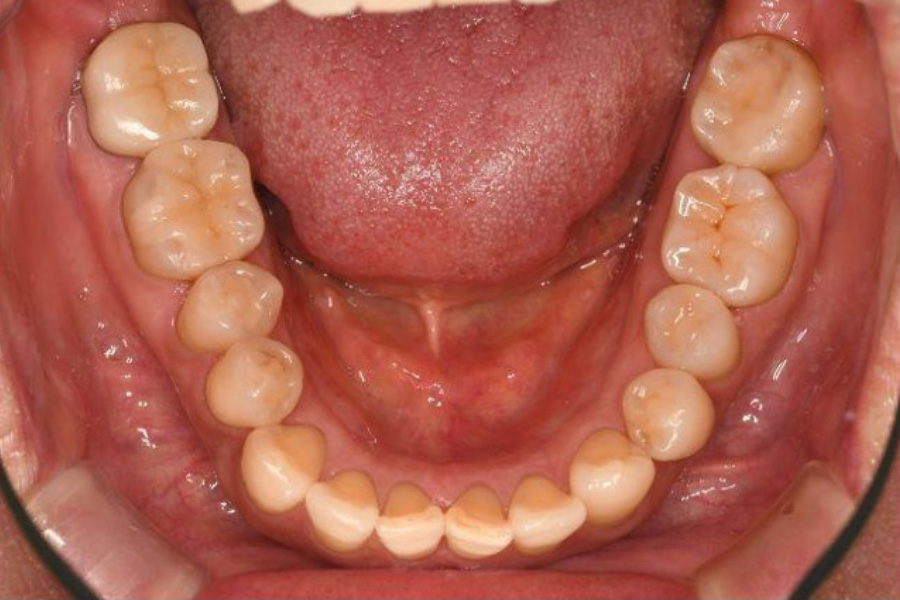

治療前

治療後

| 主訴 | 左奥歯が仕事が忙しくなると上下とも痛くなる。 毎月メインテナンスしていた歯科医院が閉院した。 歯周病含め今の状態が気になる。 全体のメインテナンスもしたい。矯正治療はやりたくない。 |

| 治療内容 | 全顎治療:歯周病治療、根管治療、 歯肉弁剥離掻爬術(フラップ手術)、 セラミック治療、ダイレクトボンディング |